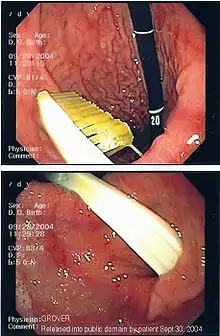

Иноро́дное те́ло (лат. corpus alienum) — с медицинской точки зрения любой чужеродный предмет, попавший внутрь организма. В узком смысле — посторонние предметы различных размеров, попавшие в глаз, ухо, нос, глотку, гортань, в пищевод или трахею (дыхательное горло). Инородное тело, даже не повредив окружающие ткани, может стать причиной смерти. Например, в результате удушья, вызванного рефлекторным спазмом голосовых связок или непрофессиональных попыток извлечения инородного тела, приведших к гибели пациента[1], а также в результате контакта со слизистой (например, батарейка может вызвать химический ожог[2]). Дети могут засунуть мелкие предметы, например бусины, в нос или ухо[3]